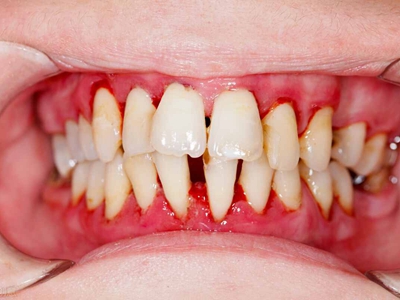

牙龈退缩多处牙龈萎缩出血图

牙龈退缩严重时,上排牙有多颗牙齿的牙龈部位发生退缩,导致牙根暴露,同时牙龈处还有出血的症状,伴有疼痛感,建议及时前往医院通过手术等手段进行治疗。